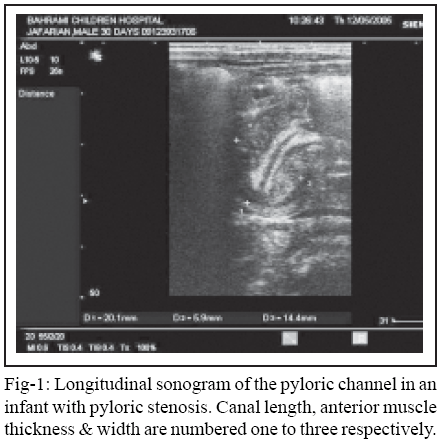

All images were obtained on a Siemens Sonoline 2 and G 50 US units with use of either 5, 7.5 or 10 MHZ transducers as sector, linear or curvilinear probes. All examination were performed by an attending radiologist with experience in children hospital. Infants were in supine or right posterior oblique position for better identification of pylorus in the longitudinal axis. Measurements were taken at the center of the pylorus, defined as the site of the pyloric lumen and identified by the double track sign of the pyloric mucosa to avert inaccuracy from tangential scans. The length of pyloric canal was measured from base of duodenal cap to the gastric antrum. The width of the canal was measured from outer edge of the muscle in both sides including the double layer of mucosa & central lumen. The muscle thickness was measured in the standard manner, from the outer wall of the pyloric muscle to the outer edge of the mucosa, which thus included the thickness of one muscle layer and excluded the mucosa and lumen. (Fig-1)

A positive diagnosis of HPS was made when a persistent olive-like mass was found in place of the normal pyloric channel, with a muscle thickness of 3 mm or more (Figure 1). Three mm is used to including more cases and not missing them for surgery. Positive findings were confirmed surgically.